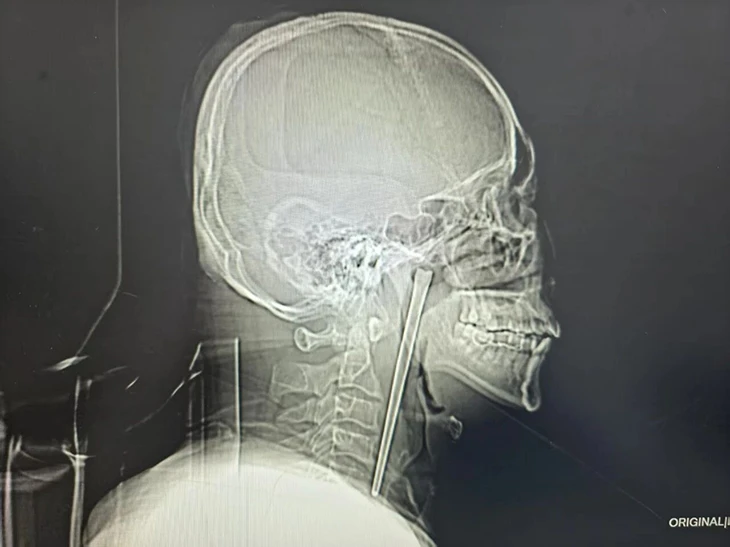

Ảnh chụp X-quang chiếc đũa dài khoảng 12 cm nằm trong cổ họng bệnh nhân. Ảnh: YouTube

Một người đàn ông Trung Quốc đã sống suốt 8 năm với một chiếc đũa kim loại mắc trong cổ họng trước khi được phẫu thuật lấy ra thành công. Theo báo cáo bệnh án được công bố gần đây, bệnh nhân, được xác định là ông Wang, 46 tuổi, đã vô tình nuốt phải một chiếc đũa kim loại dài khoảng 12 cm trong bữa ăn vào năm 2018 khi đang trong tình trạng say rượu. Sau sự cố, ông đã đến cơ sở y tế kiểm tra nhưng từ chối phẫu thuật do lo ngại phải mổ mở vùng cổ.

Các bác sĩ tại Bệnh viện Trung tâm thành phố Đại Liên, tỉnh Liêu Ninh, đã tiến hành thăm khám và xác định dị vật vẫn nằm trong cổ họng của bệnh nhân sau nhiều năm. Theo bác sĩ Huang Weipeng, người trực tiếp điều trị, ban đầu ông cho rằng sự việc mới xảy ra, nhưng bất ngờ khi bệnh nhân cho biết dị vật đã tồn tại trong cơ thể suốt 8 năm.

Nhóm phẫu thuật đã lựa chọn phương pháp can thiệp ít xâm lấn, đưa dụng cụ qua đường miệng để lấy dị vật thay vì tiến hành mổ mở vùng cổ. Ca phẫu thuật diễn ra thành công, chiếc đũa kim loại được lấy ra an toàn.